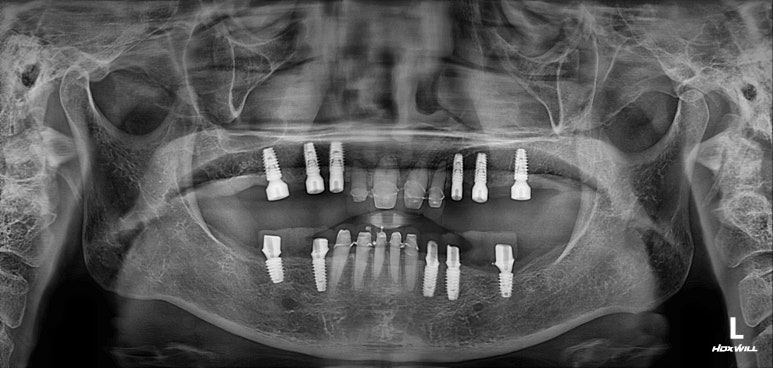

엑스레이는 지난 내원 때 찍었던 것인데, 한가지 알 수 있는 것은?

다행히도 잇몸뼈가 건강하고 많아서 충분히 임플란트로 치료가 가능하다는 것!!

엑스레이 또한 빼놓을 수 없죠!!

적절한 위치에 심어진 임플란트는 곧 적절한 임플란트 크라운으로 이어지게 되고,

당연히 모양도 예쁘게 제작되겠지만, 음식물이 끼는 것도 최소화됩니다.